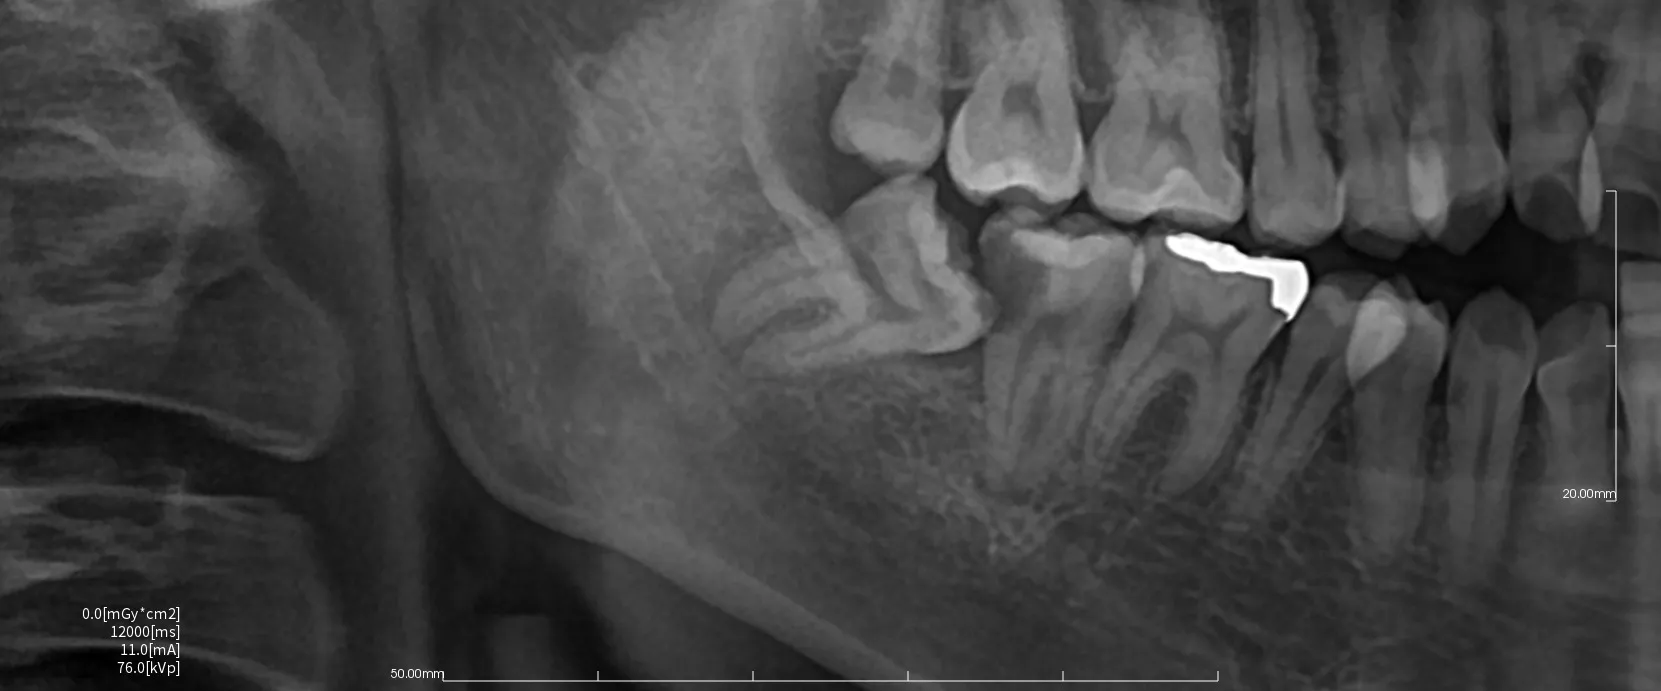

まず親知らずのレントゲン写真を2つお見せします。

どちらも横向きに生えた親知らずですが、抜歯の難易度は大きく異なります。

難易度ではレントゲン写真1>レントゲン写真2となります。

・横向きであることは同じですが、角度は大きく違います。

写真1は下に向かっている。写真2は上に向かっている。

抜歯は口腔内から治療を行うために、上に向いている方が器具が届きやすく、目で見える範囲で治療を行うことができます。

・骨に埋まっている範囲は写真1>写真2。

骨に埋まっている範囲が大きければ大きいほど骨を切削して掘り出す必要が出てきます。

周りの骨を削合すれは当然創傷は大きくなり、腫れや出血、痛みなどの症状も出やすくなります。

・下顎管(神経や血管のある管)との距離や歯の接している範囲

下顎管の損傷は神経麻痺のリスクや大量出血のリスクが大きくともなってきます。

近ければ近いほど、範囲が多ければ多いほど慎重に治療を行う必要があるために抜歯時間も長くなる傾向にあります。

・歯根の開き方

歯根は写真1は単根と言って1つにまとまっています。しかし写真2では2根にはっきりと分かれていてカニの爪のように彎曲もしています。

この場合は写真2の方が難易度は上がってきます。